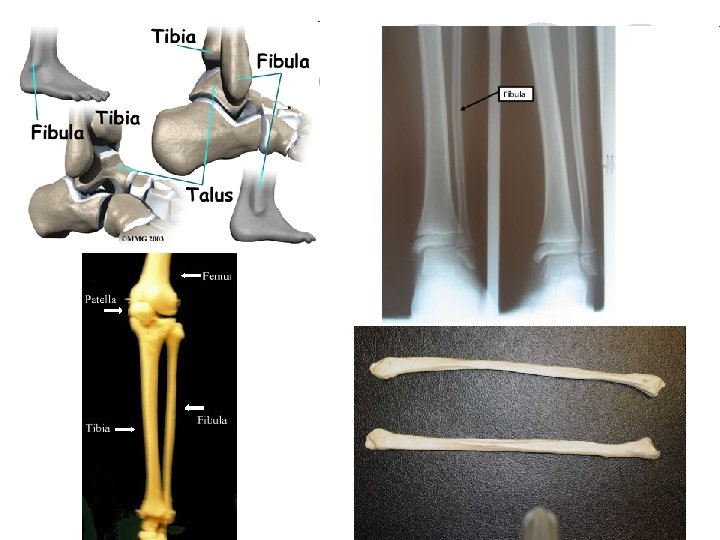

Kostra dolní končetiny – OSSA MEMBRI INFERIORIS Pletenec pánevní – PELVIS l Viz. výše popsáno l l l l Stehno – FEMUR Kost stehenní – FEMUR, OS FEMORIS Hlavice kosti stehenní – CAPUT FEMORIS Krček kosti stehenní – COLLUM FEMORIS Velký chocholík – TROCHANTER MAJOR Malý chocholík – TROCHANTER MINOR Kloubní hrboly – CONDYLUS MEDIALIS ET LATERALIS

Kostra dolní končetiny – OSSA MEMBRI INFERIORIS l Čéška – PATELLA l Nachází se ve šlaše čtyřhlavého svalu stehenního l Je součástí kolenního kloubu

Kostra dolní končetiny – OSSA MEMBRI INFERIORIS l Bérec l l l l – CRUS Kost holenní – TIBIA Kloubní hrboly – CONDYLUS MEDIALIS ET LATERALIS Přední hrana – MARGO ANTERIOR Vnitřní kotník – MALLEOLUS MEDIALIS Kost lýtková – FIBULA Hlavice – CAPUT FIBULAE Zevní kotník – MALLEOLUS LATERALIS